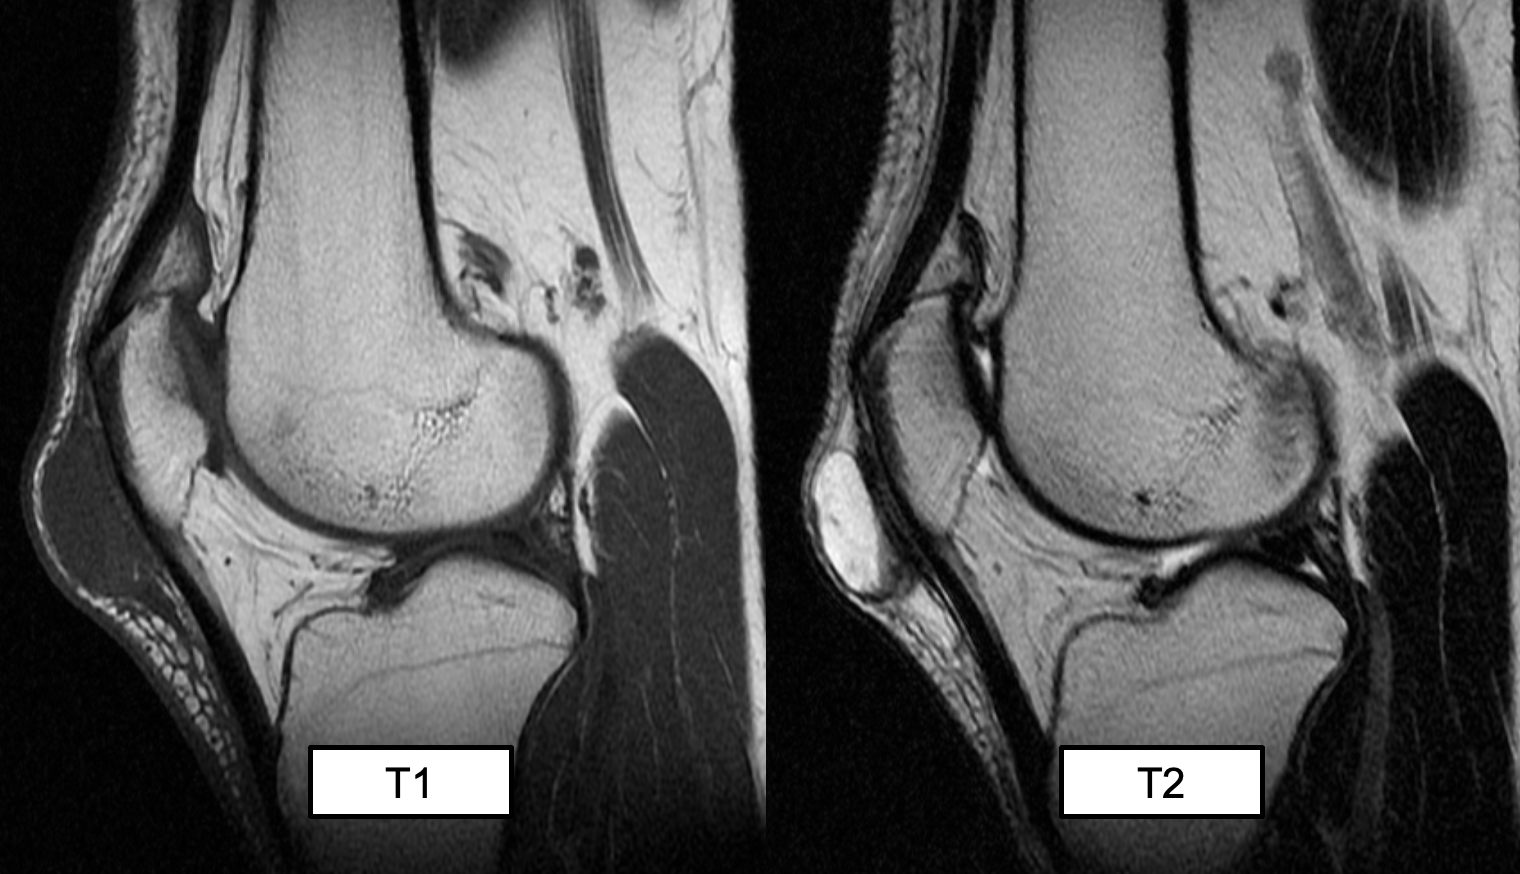

suprapatellar bursitis (likely not examined)

(T2 MRI)

prepatellar bursitis

A round high signal intensity structure, consistent with a fluid given the T2 weighted MRI, is located superficial to the patella ligament

(inflammation within the prepatellar bursa)

(prepattar = most common)